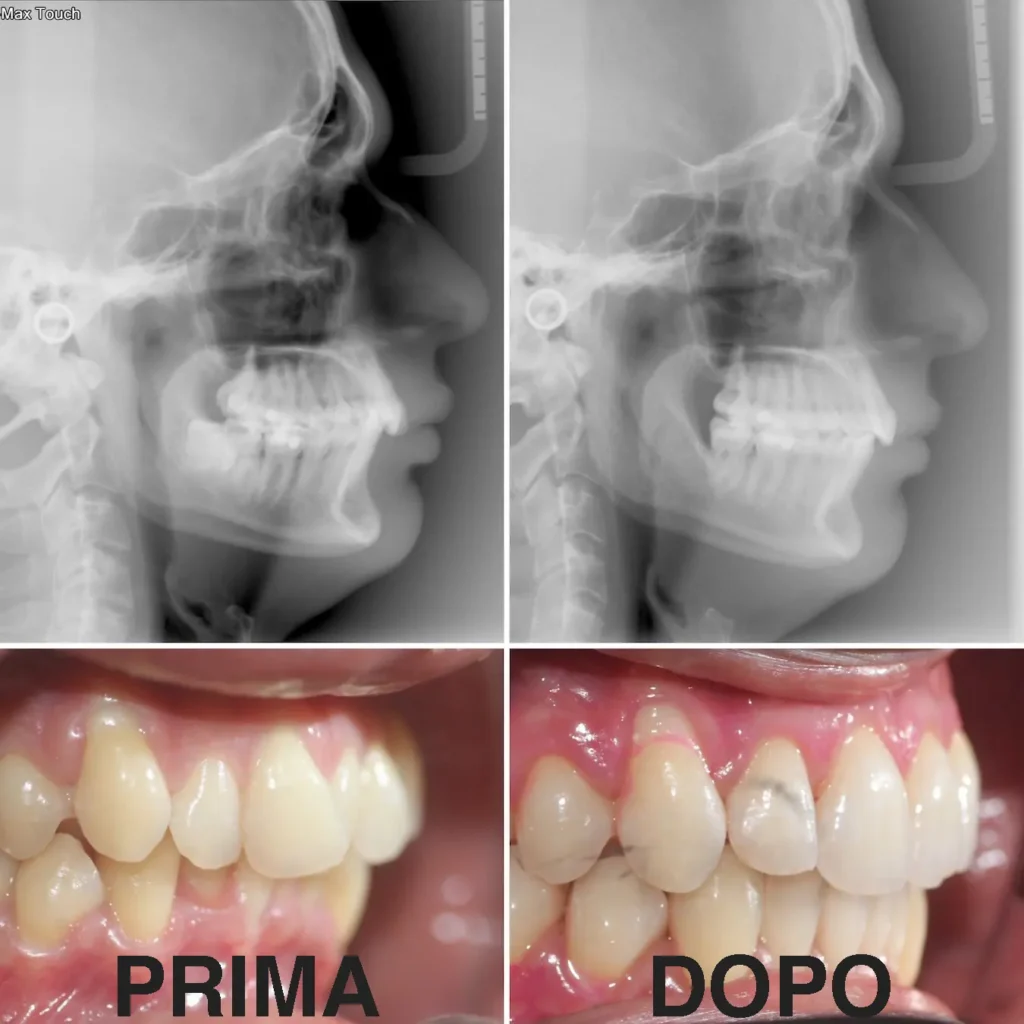

In questo caso clinico, vediamo come un paziente adulto ha risolto un affollamento importante grazie all’apparecchio linguale WIN.

Nel caso analizzato, il paziente presentava un affollamento marcato sia nell’arcata superiore che in quella inferiore.

Risultati ottenuti

Il risultato finale è stato molto positivo.

I denti sono risultati ben allineati e il sorriso completamente trasformato. Il paziente ha notato anche un miglioramento nella pulizia quotidiana e nel comfort durante la masticazione.

Un aspetto importante è la soddisfazione del paziente. Tutto il trattamento è avvenuto senza che l’apparecchio fosse visibile.